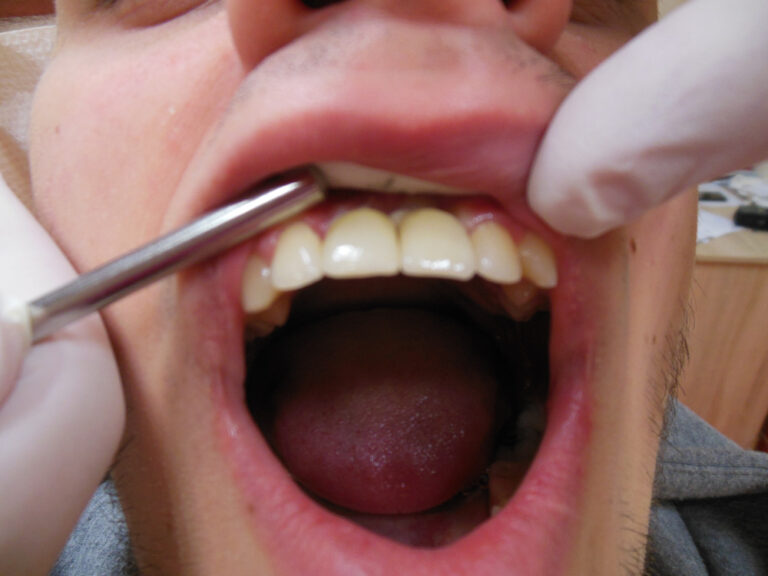

Przykłady implantologii

Zastosowanie implantoprotetyki w przypadku gdy klasyczna protetyka nie sprawdza się.